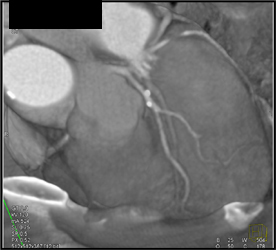

Normal Coronary Arteries